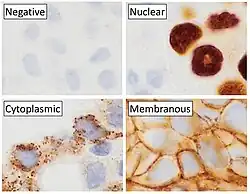

- ↑ Image by Mikael Häggström, MD. Reference for terminology: Anjelica Hodgson, M.D., Carlos Parra-Herran, M.D. "p16". Pathology Outlines.